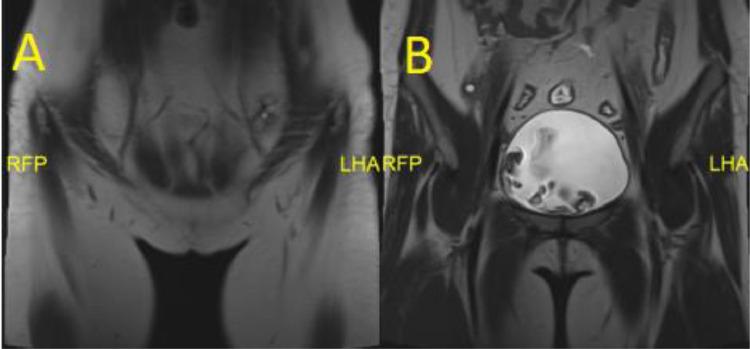

Mayer-Rokitansky-Küster-Hauser syndrome (MRKH) is a congenital disorder syndrome characterized by failure of the uterine and vaginal organs to develop normally. The prevalence of MRKH is estimated to occur in about 1 in 5000 of female live births. A 25-year-old female patient comes to a general obstetric and gynecological polyclinic with complaints of not being able to menstruate at all since birth. There is a history of vaginal discharge but it is neither viscous nor had an odor. On ultrasound examination, the structure of the uterus and ovaries was not found in a normal place. On follow up MRI examination showed agenesis of the uterus and proximal two-third of the vagina accompanied by abnormal positioning of both ovaries, thus supporting to atypical form of MRKHS. The patient is not given drug therapy, but she was planned to transplant the uterine organs. This case report suggests MRKH syndrome can be characterized by ectopic ovaries and a uterus that is not fully developed and can also be accompanied by agenesis of the vaginal organs. Pelvic ultrasound is the main modality chosen to be performed in patients with symptoms of primary amenorrhea. When pelvic organs cannot be visualized properly, it will be performed MRI examination. MRI examination is known to have sensitivity and specificity up to 100% in diagnosing MRKH syndrome. This case report describes a 25-year-old woman with primary amenorrhea with MRKH syndrome. MRI is a sensitive and specific examination to confirm the diagnosis.

迈耶-罗基坦斯基-库斯特-豪泽综合征(MRKH)是一种先天性疾病综合征,其特征是子宫和阴道器官发育异常。据估计,MRKH在每5000例女性活产中约有1例发生。一名25岁的女性患者来到一家综合妇产科门诊,主诉自出生以来一直无法月经来潮。有白带病史,但白带既不粘稠也无异味。超声检查未在正常位置发现子宫和卵巢结构。后续的MRI检查显示子宫和阴道近端三分之二发育不全,同时双侧卵巢位置异常,从而支持非典型形式的MRKHS。该患者未接受药物治疗,但计划进行子宫器官移植。本病例报告表明,MRKH综合征的特征可能是卵巢异位、子宫发育不全,还可能伴有阴道器官发育不全。盆腔超声是对原发性闭经患者进行检查的主要方式。当盆腔器官无法清晰显示时,将进行MRI检查。已知MRI检查在诊断MRKH综合征时的敏感性和特异性高达100%。本病例报告描述了一名患有MRKH综合征的原发性闭经25岁女性。MRI是确诊的一项敏感且特异的检查。